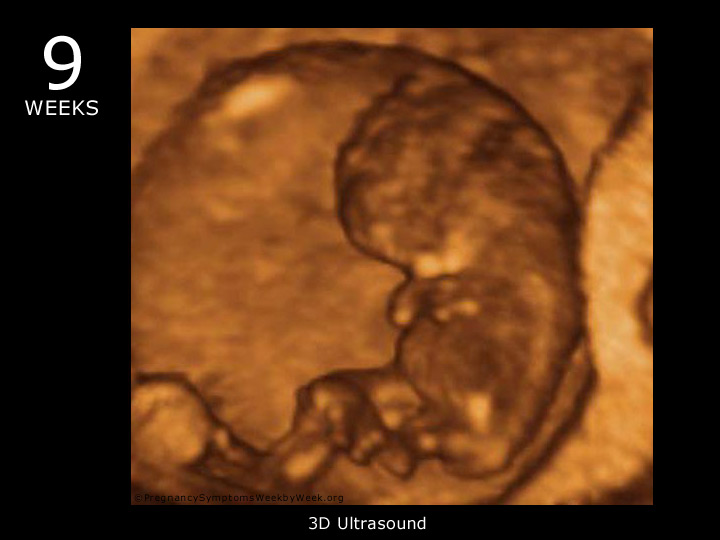

Embryonic and fetal development occurs quickly during the first trimester of your pregnancy (weeks 6-12). The following images provide an ultrasound view to help you track and visualize development over your first trimester of pregnancy.